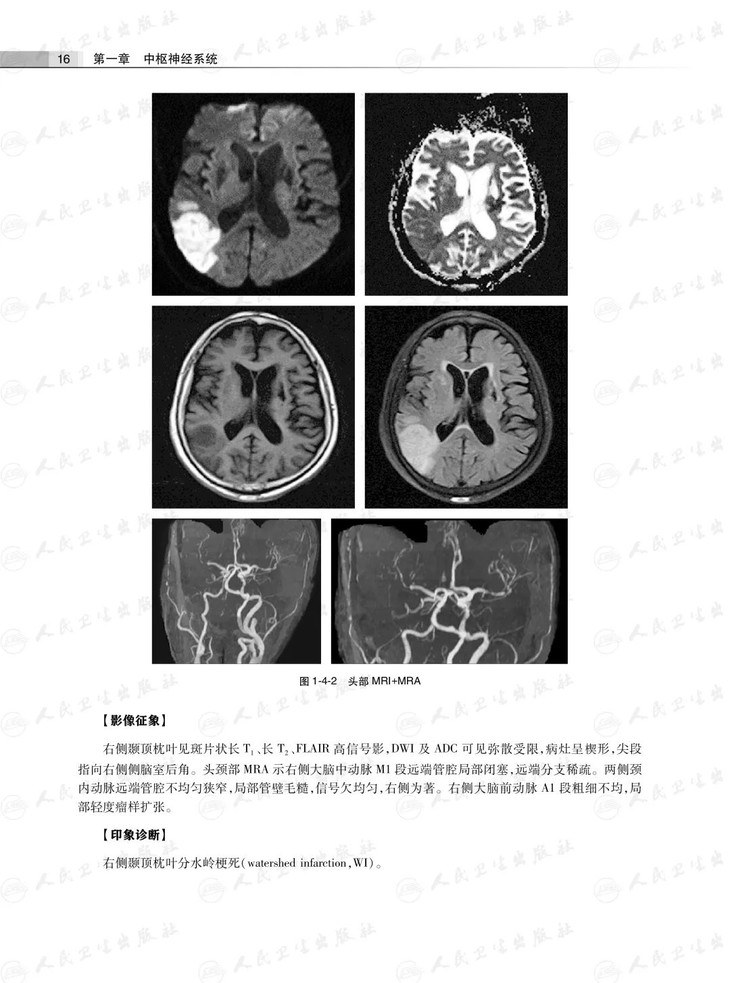

第四节血管性病变